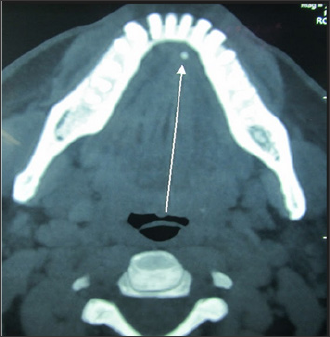

A 58 year old female reported with a chief complaint of intermittent swelling in left submandibular region. The swelling was related to meals and persisted for 2-3 hours after food. It was variable in size and occurrence. On examination, there was mild swelling in submandibular region (Figure 1). Ductal orifice was slightly reddish and tender signifying inflammation. Expressed saliva was normal in appearance and consistency but the salivary flow was relatively reduced compared to contra lateral side. Clinical diagnosis of left submandibular sialolith was made. A computerised tomogram revealed a 2.4mm radiopaque mass in anterior part of the left Wharton's duct (Figure 2a-2c). However, the calculus was not visible or palpable. The sialolith was removed intra orally under local anesthesia. The surgical technique has already been discussed (Figure 3-7).

Figure 2a: Axial section of CT showing sialolith.